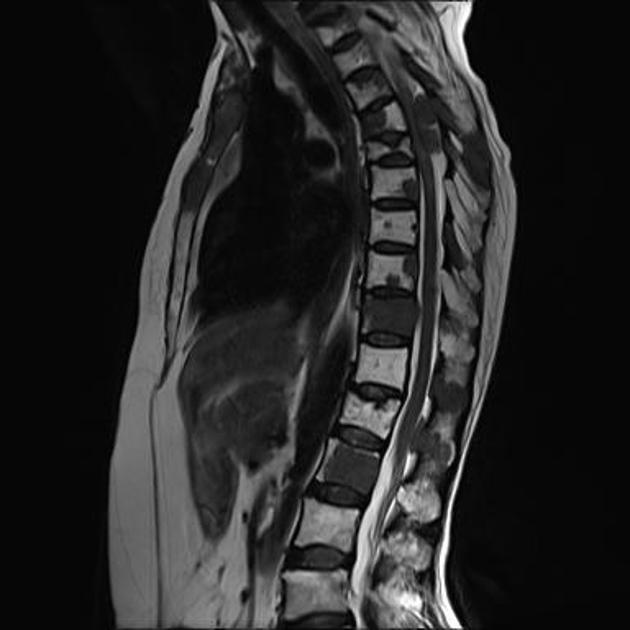

📌 2. Diferenças na Imagem por Ressonância

| Característica |

Metástase |

Nódulo |

Lesão |

| Tamanho |

Variável, muitas vezes múltiplas. |

Menor que 3 cm, geralmente única. |

Qualquer tamanho. |

| Morfologia |

Arredondada, realce anelar ou heterogêneo. |

Oval ou arredondada, realce variável. |

Pode ser difusa ou irregular. |

| Sinal na RM |

Hipo T1, hiper T2, edema vasogênico, realce pós-contraste. |

Depende do conteúdo (sólido ou cístico). |

Variável, depende da etiologia. |

| Distribuição |

Frequentemente múltiplas em locais típicos. |

Localizado. |

Única, múltipla ou difusa. |